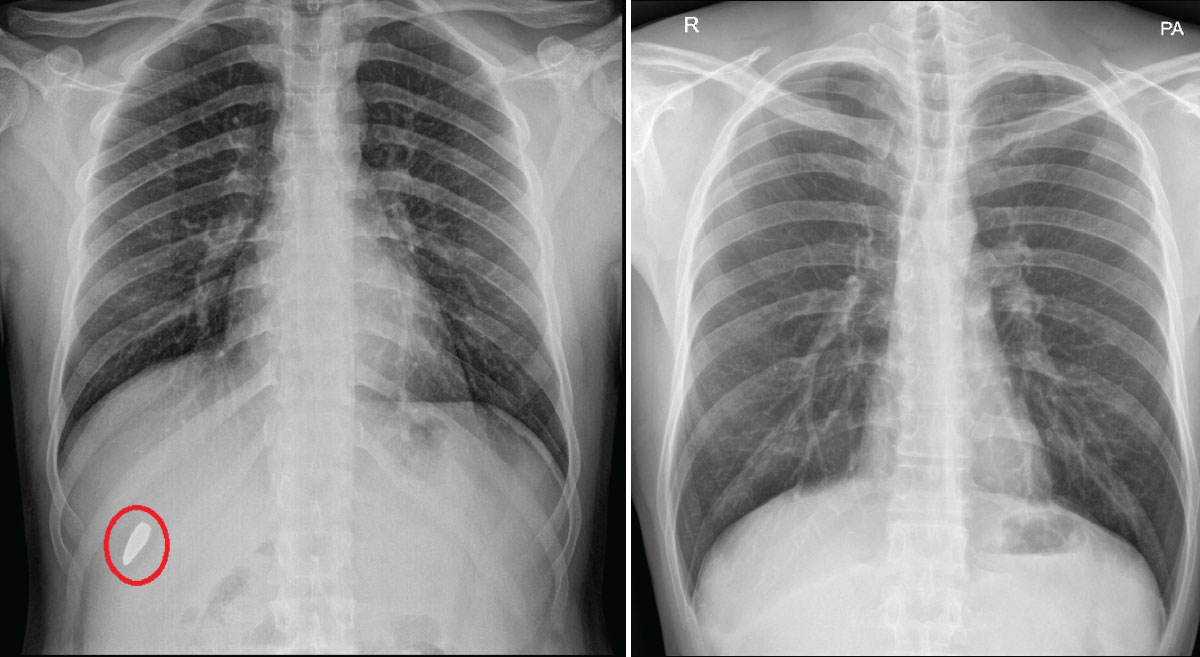

Bullet

Yemeni Patient's Lung Restored...

A rare case of extraction of a bullet from the lungs A rare case of extraction of a bulle...

Dr. Divakar Bhat 28 March 2024